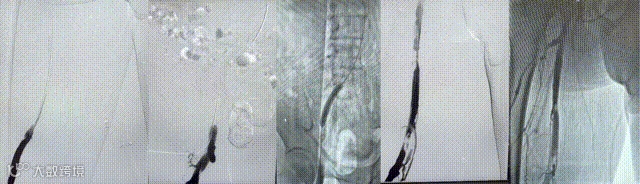

导入(10*60mm)球囊行髂静脉扩张

导入支架(14*100mm,)覆盖髂静脉狭窄处,再次造影见狭窄消失,股静脉回流通畅,原滤器内未见明显血栓形成,无造影剂外溢。拔管,穿刺点压迫止血,加压包扎。麻醉满意,术后患者安返病房。

(四)导入球囊(10*80mm)扩张髂股静脉,再次造影见髂总静脉闭塞

(五)导入支架(14*90mm)覆盖髂总静脉压迫处,再次造影见髂股静脉通畅。拔除导管及导管鞘,术中出血约 300ml,术后患者安返病房。

造影可见:髂静脉 和股静脉血流复通